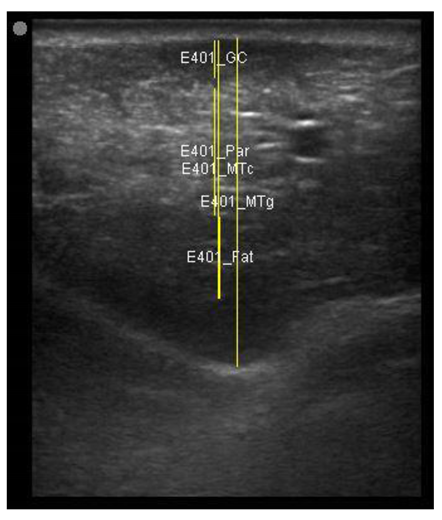

| 113 days of pregnancy (P113) Scanning depth 4.7 cm | ![]() | ![]() | MT generous: 28.9 mm MT conservative: 25.9 mm Gland cistern: 3.3 mm Parenchyma: 10.9 mm Fat Pad: 10.0 mm |